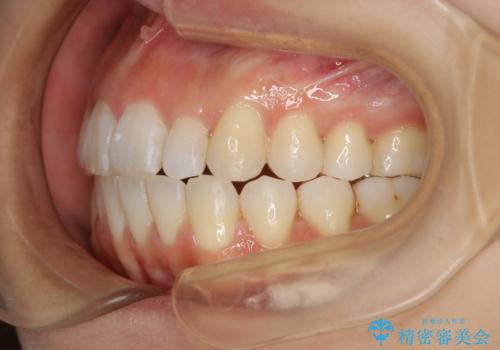

インビザラインの方法でも治せる患者様でしたが、希望によりワイヤー矯正となりました。

インビザライン治療を始めた後であっても使えないことが判明する患者様もいらっしゃいます。

当院であれば、そのような患者様の場合でも途中でワイヤー治療に切り替えて差し上げることが可能となります。